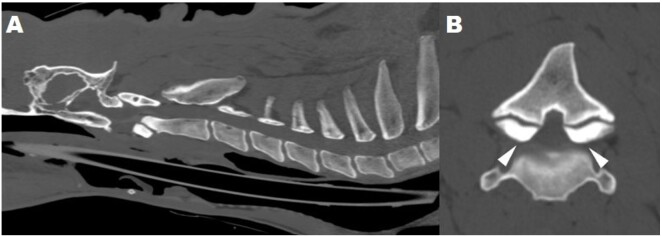

An 11-year-old male Bengal tiger (Panthera tigris tigris) was referred for a 2-week history of ambulatory tetraparesis, generalized ataxia, and hypermetric gait, associated with mild right head tilt and spontaneous proprioceptive deficit on the right forelimb. Neuroanatomical localization was C1-C5 myelopathy; cerebellum-vestibular system involvement was also considered. Hematology and serum biochemistry were unremarkable, although serum vitamin A (0.11 mg/L) was below the reference range (0.17 - 0.36 mg/L). Indirect hemagglutination test for Toxoplasma gondii was positive (antibodies titer 1:640). Computed tomography of the head and cervical column showed hypertrophic degenerative remodeling of the vertebral articular joint processes, causing severe vertebral canal stenosis and bilateral spinal cord compression at C2-C3. In addition, bilateral otitis media was present, without signs of intracranial extension of the inflammation by imaging. Brainstem auditory evoked potential test revealed a partial, bilateral conductive deafness. Cerebrospinal fluid (CSF) analysis resulted normal; CSF PCR for T. gondii was negative. A diagnosis of osseous-associated cervical spondylomyelopathy (OA-CSM) and concurrent bilateral otitis media was obtained. Glucocorticoids, movement restriction, vitamin A supplementation, and clindamycin were instituted. Four weeks later the clinical signs deteriorated, and the animal was euthanized. To the authors' knowledge this is the first report of OA-CSM in a tiger.